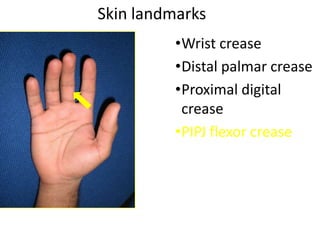

- Naming the bones, joints, tendons, nerves and skin landmarks of the hand and wrist.